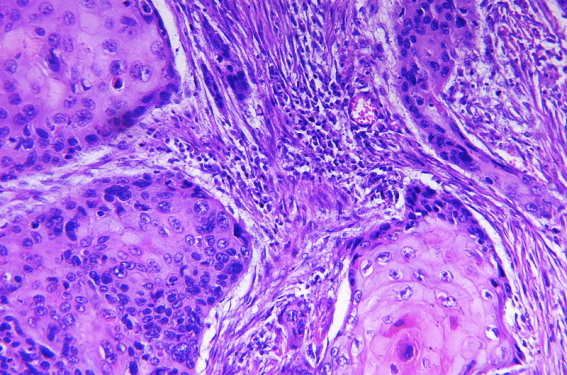

Transplantés d’organe et risque de second carcinome épidermoïde cutané

Une étude norvégienne a évalué le risque de la survenue d’un second carcinome épidermoïde cutané, de métastases et de décès liés à un carcinome épidermoïde cutané chez les patients transplantés d’organe et les patients non transplantés. Les patients...